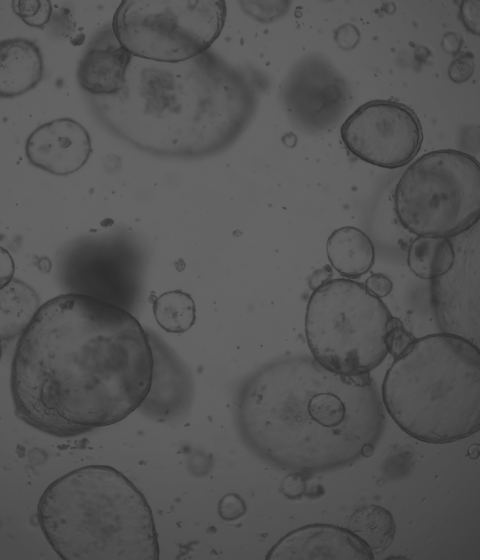

廈門(mén)?;锟萍加邢薰局铝τ?D細(xì)胞培養(yǎng)核心原材料的研發(fā)與產(chǎn)業(yè)化升級(jí),是國(guó)內(nèi)一家從科研做起,從實(shí)驗(yàn)研究中一路走來(lái)的全流程自主研發(fā)、自主生產(chǎn)的企業(yè)。目前公司的產(chǎn)品有基質(zhì)膠、類(lèi)器官培養(yǎng)基、細(xì)胞因子、3D細(xì)胞培養(yǎng)耗材、3D細(xì)胞培養(yǎng)智能顯微鏡等。公司擁有4大技術(shù)研發(fā)中心:分子克隆和細(xì)胞編輯中心、實(shí)驗(yàn)動(dòng)物中心、蛋白表達(dá)和純化平臺(tái)、類(lèi)器官質(zhì)檢系統(tǒng)和自動(dòng)化。